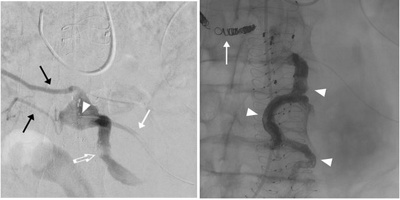

CT-Angiographie nach EVAR zeigt eine residuelle Durchblutung des Aneurysmasacks (Endoleckage).

Katheter-Embolisation

Minimalinvasive Behandlung der Endoleckage durch Katheter-Embolisation: über die grosse (Pfeilspitzen in A) und kleine (Pfeil in A) Darmarterie wird der Aneurysmasack mit einem Mikrokatheter rückwärts sondiert (weisse Pfeilspitze in B) und nachfolgend die Gefässe, die zur Endoleckage geführt haben mittels Metallspiralen (Coils, Pfeil) und Flüssigembolisat (Pfeilspitzen in C) verschlossen.